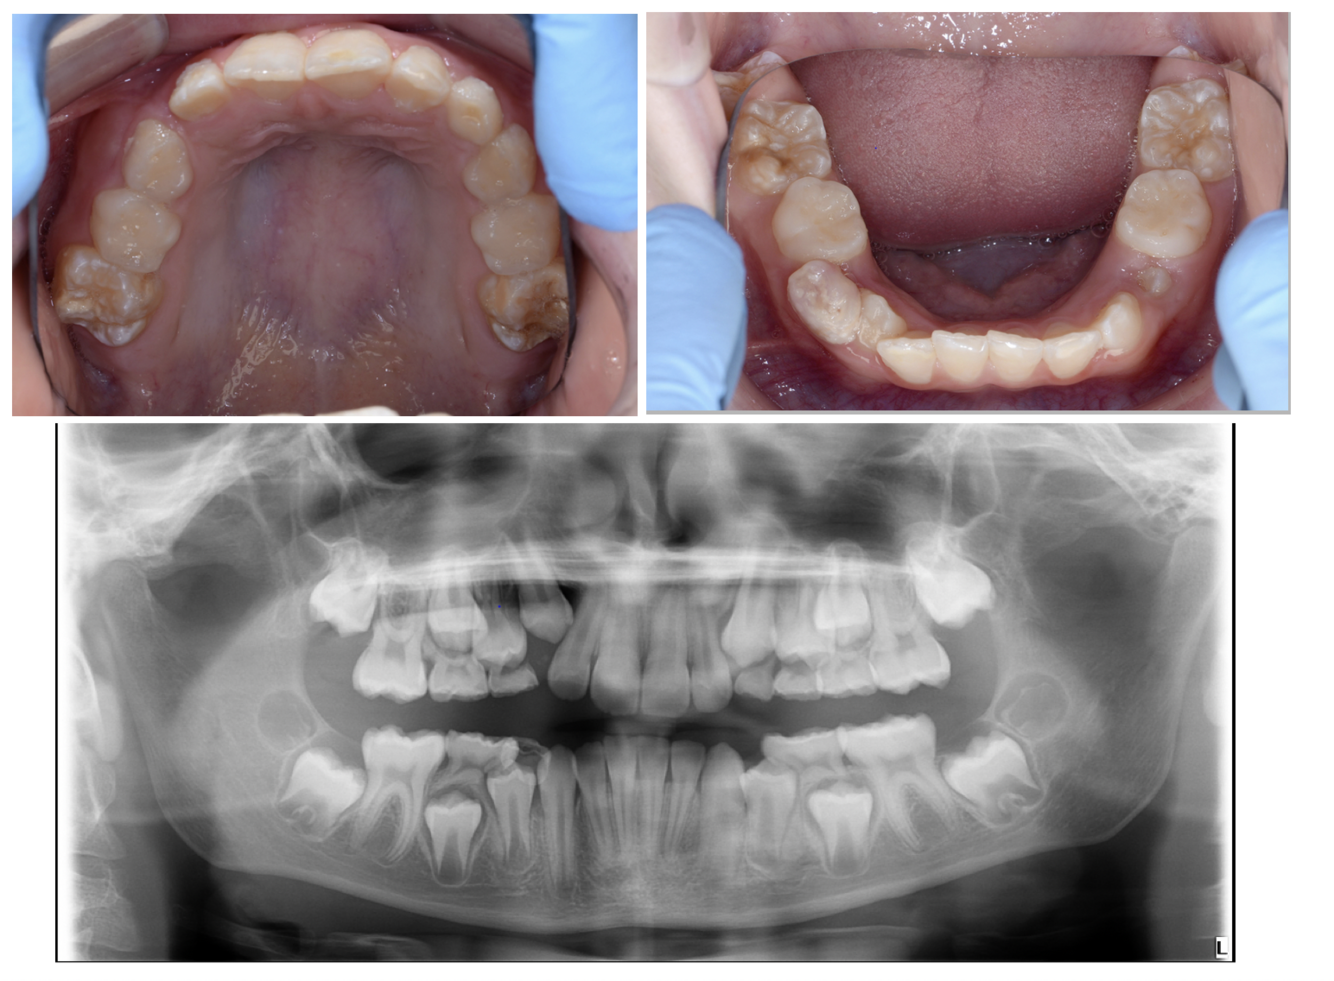

Q

• 10 year old patient

• MIH in upper and lower molars permanent molars

• Anterior tooth wear (NCTSL)

• Upper moderate crowding

• Lower mild crowding